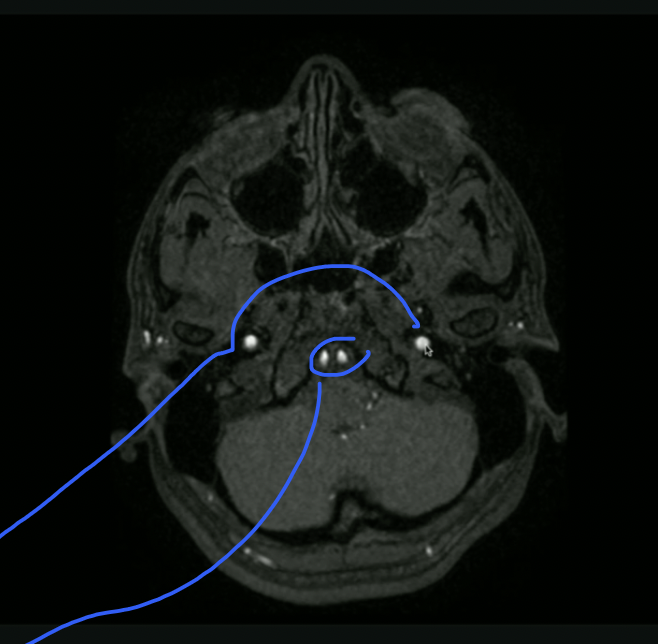

<p>What is Top + Bottom Circle + Arrow?</p>

What is Top + Bottom Circle + Arrow?

• Top: 3rd Ventricle

• Bottom: 4th Ventricle

• Arrow: Cerebral Aqueduct